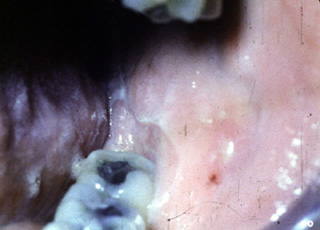

Este paciente es un varón  que está tomando Aldomet  para el tratamiento de la  hipertensión. En esta fotografía usted puede apreciar una úlcera grande en la mucosa bucal. En la periferia de la ulceración hay estrías blancas similares al liquen plano erosivo. Estas ulceraciones son dolorosas y ocurren con la tomo de dicha droga.